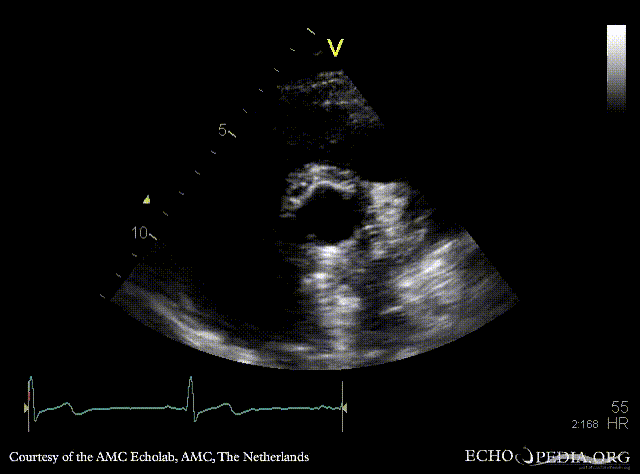

Bentall and aortic valve prosthesis

Courtesy of: AMC Echolab, AMC, The Netherlands

PSAX: aortic valve prosthesis and Bentall in situ PSAX with Color Doppler